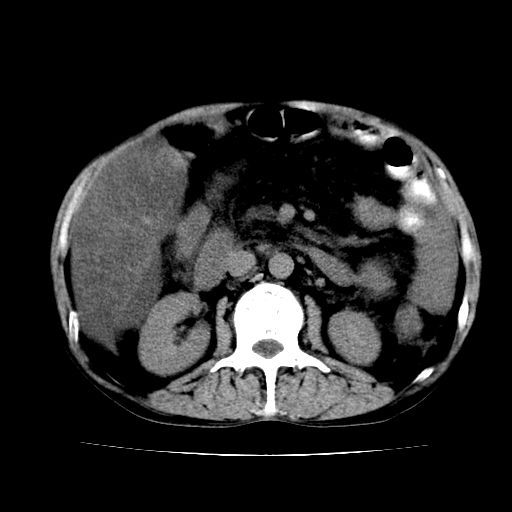

男,55岁,发现“肝硬化”5年,现腰疼、腹胀10余日,巩膜黄染、腹稍胀,肝肋下3指,质硬无压疼,移动性+,血生化:总胆、直胆、间胆均升高。

肝脾肿大,脂肪肝,腹水。建议增强除外肝癌。

1.脂肪肝

2.腹水

3.肝脾肿大

4.肝癌?

建议增强